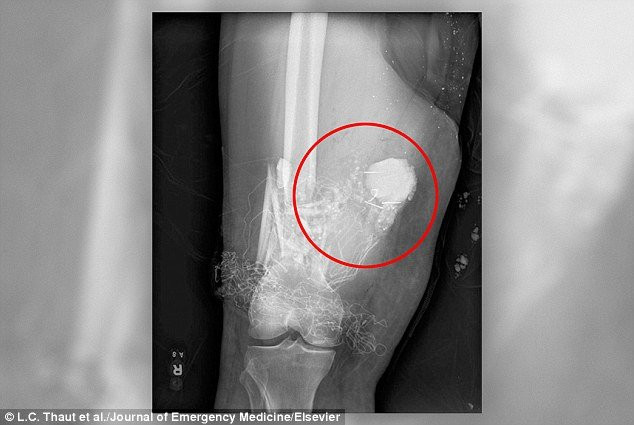

Tuy nhiên, khi người bệnh đến Trung tâm Quân y San Antonio để thăm khám lấy pháo hoa mắc kẹt ra khỏi cơ thể, kết quả X-quang cho thấy: "Pháo hoa đã đâm xuyên bắp đùi phải và có thể nổ bất cứ lúc nào".

Kết quả chụp X-quang cho thấy pháo hoa đâm xuyên bắp đùi.